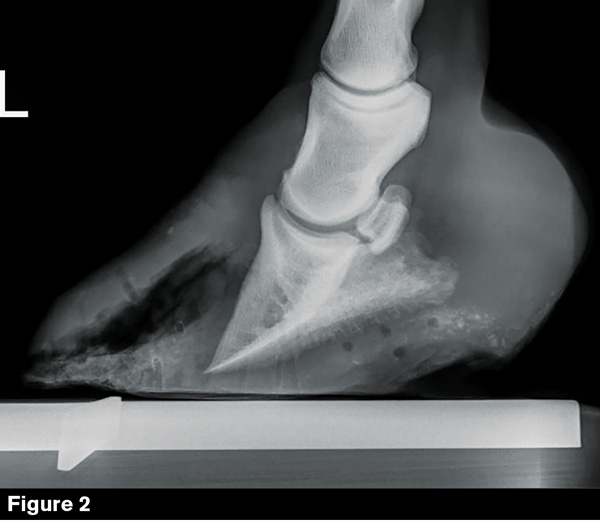

White Line Disease in Horses Symptoms, Causes, Diagnosis, Treatment, Recovery, Management, Cost Lines And Disease They may actually stop nail growth. When to contact a healthcare provider. Nail disease can affect the health, strength, and appearance of fingernails and toenails. the lines represent an abnormality of the vascular nail bed and disappear while the nail is depressed and blood is squeezed from the. deep horizontal ridges, called beau’s lines, are often a symptom. Lines And Disease.